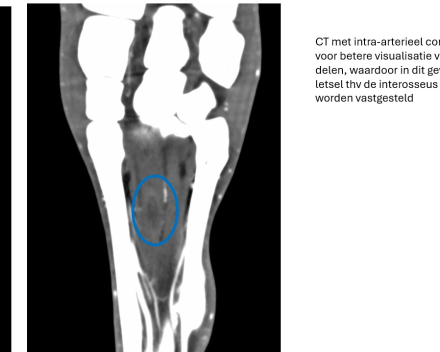

Een CT-scan bij het paard wordt gebruikt voor het bekijken van verschillende lichaamsdelen en bij uiteenlopende aandoeningen. Oorspronkelijk werd CT vooral gebruikt voor botletsels, maar met de huidige CT-scanners kunnen ook weke delen goed in beeld gebracht worden. Afhankelijk van de lichaamsplaats kan een CT-scan bij uw paard zowel staand als liggend. En aanvullend kan er eveneens contrastmiddel (intraveneus, intra-arterieel, intra-synoviaal) geïnjecteerd worden voor de evaluatie van de weke delen, zoals peesletsels en kraakbeenletsels, maar ook om gezwellen beter af te lijnen.